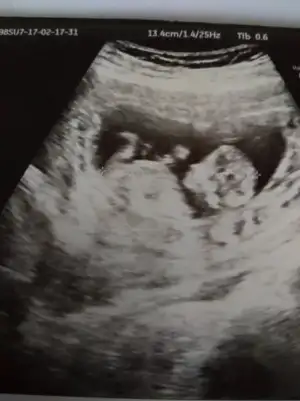

kız gibi canım. Şöyle usg resmini eline aldığında eğer karından usg ise bebek kesenin sağına yakınsa kız soluna yakınsa erkek, vajinal usg ise tam tersi. Buarada sesin ultrason resmi benimkine çok benziyo bebeğin kesedeki konumu olarak

Kizlar bugun tekrar gittim doktora,8 haftalikken bebek kesenin sagindaydi.simdi 10 haftalik,cok kipirdak sanirim sola yaklasmis.bu kese ve cinsiyet konusu kac haftalikken dogru oluyor? Bidaha bakarmisniz bana